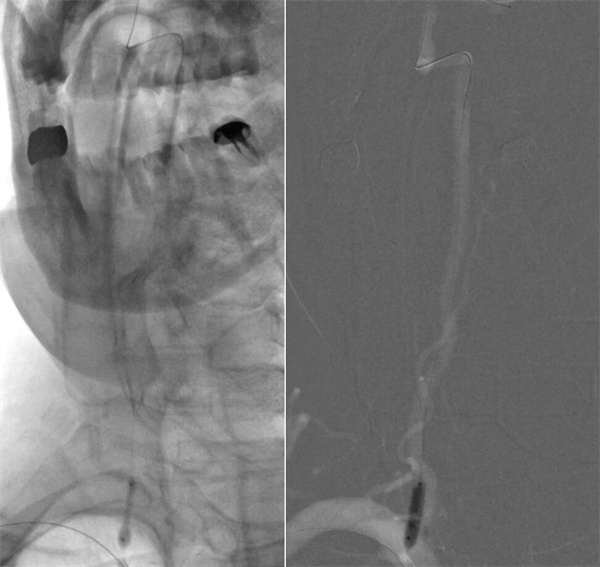

经过充分术前准备,介入手术在导管室护士、技师及麻醉师的全力配合下,择期在全麻下进行。术中,神经外科副主任医师刘磊利用“四步走”的方式,为患者进行手术:

第一步,通路建立与保护。经股动脉穿刺建立通路。考虑到狭窄程度重,导引导管难以通过椎动脉开口,强行通过易导致斑块脱落,甚至损伤血管内膜致夹层。刘磊副主任医师应用小球囊穿梭技术顺利引导导引导管通过椎动脉起始狭窄处,到达指定位置。

第二步,处理动脉瘤,拆除不定时炸弹。医生将微导管超选择进入动脉瘤腔内,依次填入数枚弹簧圈,直至动脉瘤完全栓塞,不再显影。因为动脉瘤瘤颈宽,故于载瘤动脉内植入了支架以达到致密栓塞,降低复发率。

第三步,解除狭窄,恢复血流。选择合适尺寸的球囊扩张式支架,精准释放于右侧椎动脉起始部狭窄段。